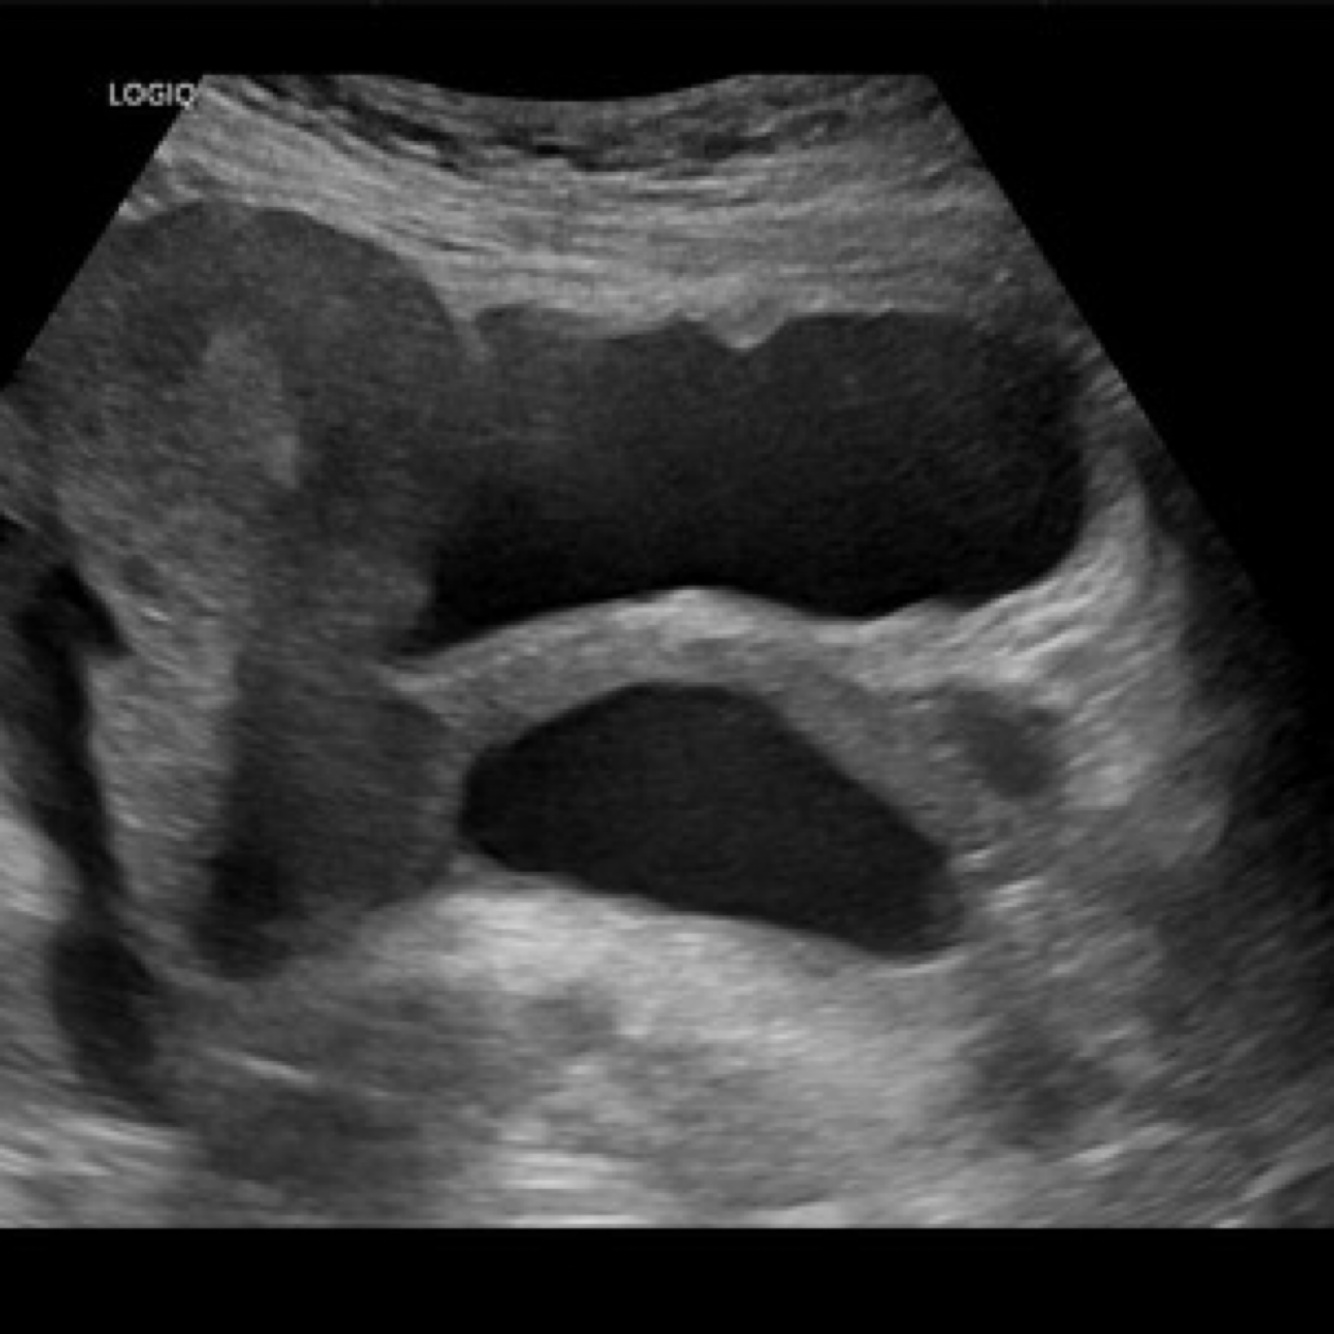

is a temporary endocrine structure formed in the ovary after ovulation from the remnants of the Graafian (mature) follicle. It plays a vital role in maintaining early pregnancy. Sustained by hCG from the trophoblast for 10-12 weeks and then degenerates into corpus albicans (scar-like tissue).

Corpus Luteum